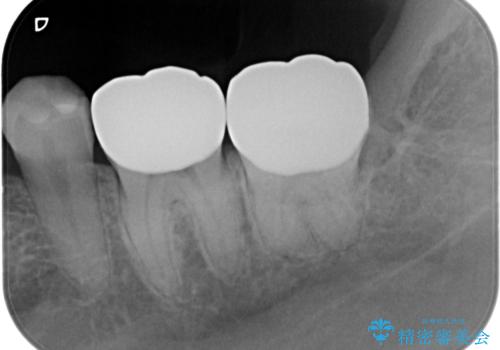

プラスチックがすり減り歯の高さが少ないため、薄くても丈夫なセラミックのかぶせ物(クラウン)を選びました。

外れないようにする工夫はほかにも連結といって2本つなげるという方法がありますが、今回は単冠といってフロスが通るように1本1本分かれた自然な形でかぶせました。

- 19.8万円(ヴェレッツァクラウン×2本、仮歯×2本)費用は治療当時の料金となります